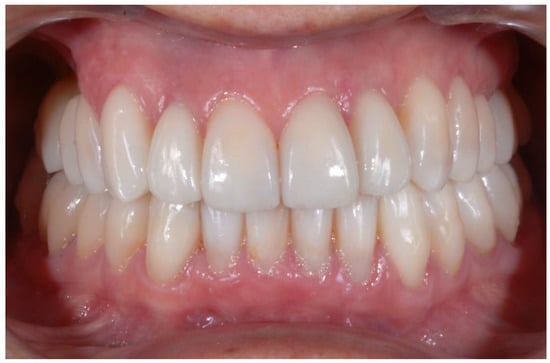

| Parameter Examined | Clinical Significance | Result Obtained |

|---|---|---|

| Smile symmetry | Smile symmetry refers to the mirror agreement between the two sides of the mouth but can also consider the bi-pupillary line, the incisal line, and the labial commissure. | YES |

| Horizontal symmetry | It originates from the presence of similar elements placed in a regular sequence, as verified in a dentition with teeth well aligned in the horizontal plane. | YES |

| Vertical symmetry | Recall the same principle as above, referring to the vertical direction. | YES |

| Repeated report | It indicates the division of space into portions that may not be identical in shape and size but arranged to generate a harmonious connection between them. This is what is verified between opposing hemiarches with well-arranged teeth, inspiring a sense of order and balance. | YES |

| Prospective effect | The contour of the buccal surface and the alignment of the inclined planes of the teeth is decisive in generating a correct perspective effect. The different length or strong color difference of even one element can impair the perspective effect and compromise the sense of harmony of the whole. | YES |

| Lip height | Useful distinction in static and dynamic harmony. The average height of the upper vermilion is 7.1 mm in the male and 7.7 mm in the female. The lower vermilion is normally more extensive, about 10 mm on average; these are statistical values, with wide individual variations. | YES |

| Lip line | The height of the upper lip, relative to the upper central incisors, can be classified as low, medium, or high, on the basis of the amount of crown exposure. | YES |

| Smile line | Smile line is a curved line passing through the incisal margin of the upper incisors, parallel to the inner margin of the lower lip. | YES |

| Curvature of the upper lip | With superior convexity, it extends from the center toward the lateral triangular spaces. When rectilinear or worse with inverted convexity, it gives the subject a sad and unattractive expression. | YES |

| Frontal axial alignment | The smooth slope of the long axis of the front elements helps generate a sense of regularity. | YES |

| Tooth alignment in the arch | Recalls the anatomical harmony represented by the correct positioning of teeth in the center of the alveolar ridge. | YES |

| Contact point alignment | In the anterior sectors, the contact points are located near the incisal third and their sequence defines a curvilinear pattern. | YES |

| Color | Color is one of the cardinal elements of dental aesthetic recovery. It must always be evaluated in a much broader context, involving many other periodontal, labial, and skin parameters of the patient. | YES |

| Gingival scalloping | Gingival parabolas are decisive for the aesthetic effect of the frontal group. Orthodontic treatment can contribute to their harmonization. | YES |

| Negative space | A restrained smile enhances the characteristics of the teeth, while an excessive smile imparts an unattractive sense of emptiness. | YES |

| Arch geometry | There are several types of arch form related to individual craniofacial conformation that must be recreated or respected by orthodontic treatment. | YES |

| Buccal corridors o black tunnels | A restrained smile enhances the characteristics of the teeth, while an excessive smile imparts an unattractive sense of emptiness. | YES |

| Fibonacci golden proportion | It evaluates proportions by relating harmony to numerical values. In the dental field, it can find application in the evaluation of various dental and facial morphological parameters. | YES |